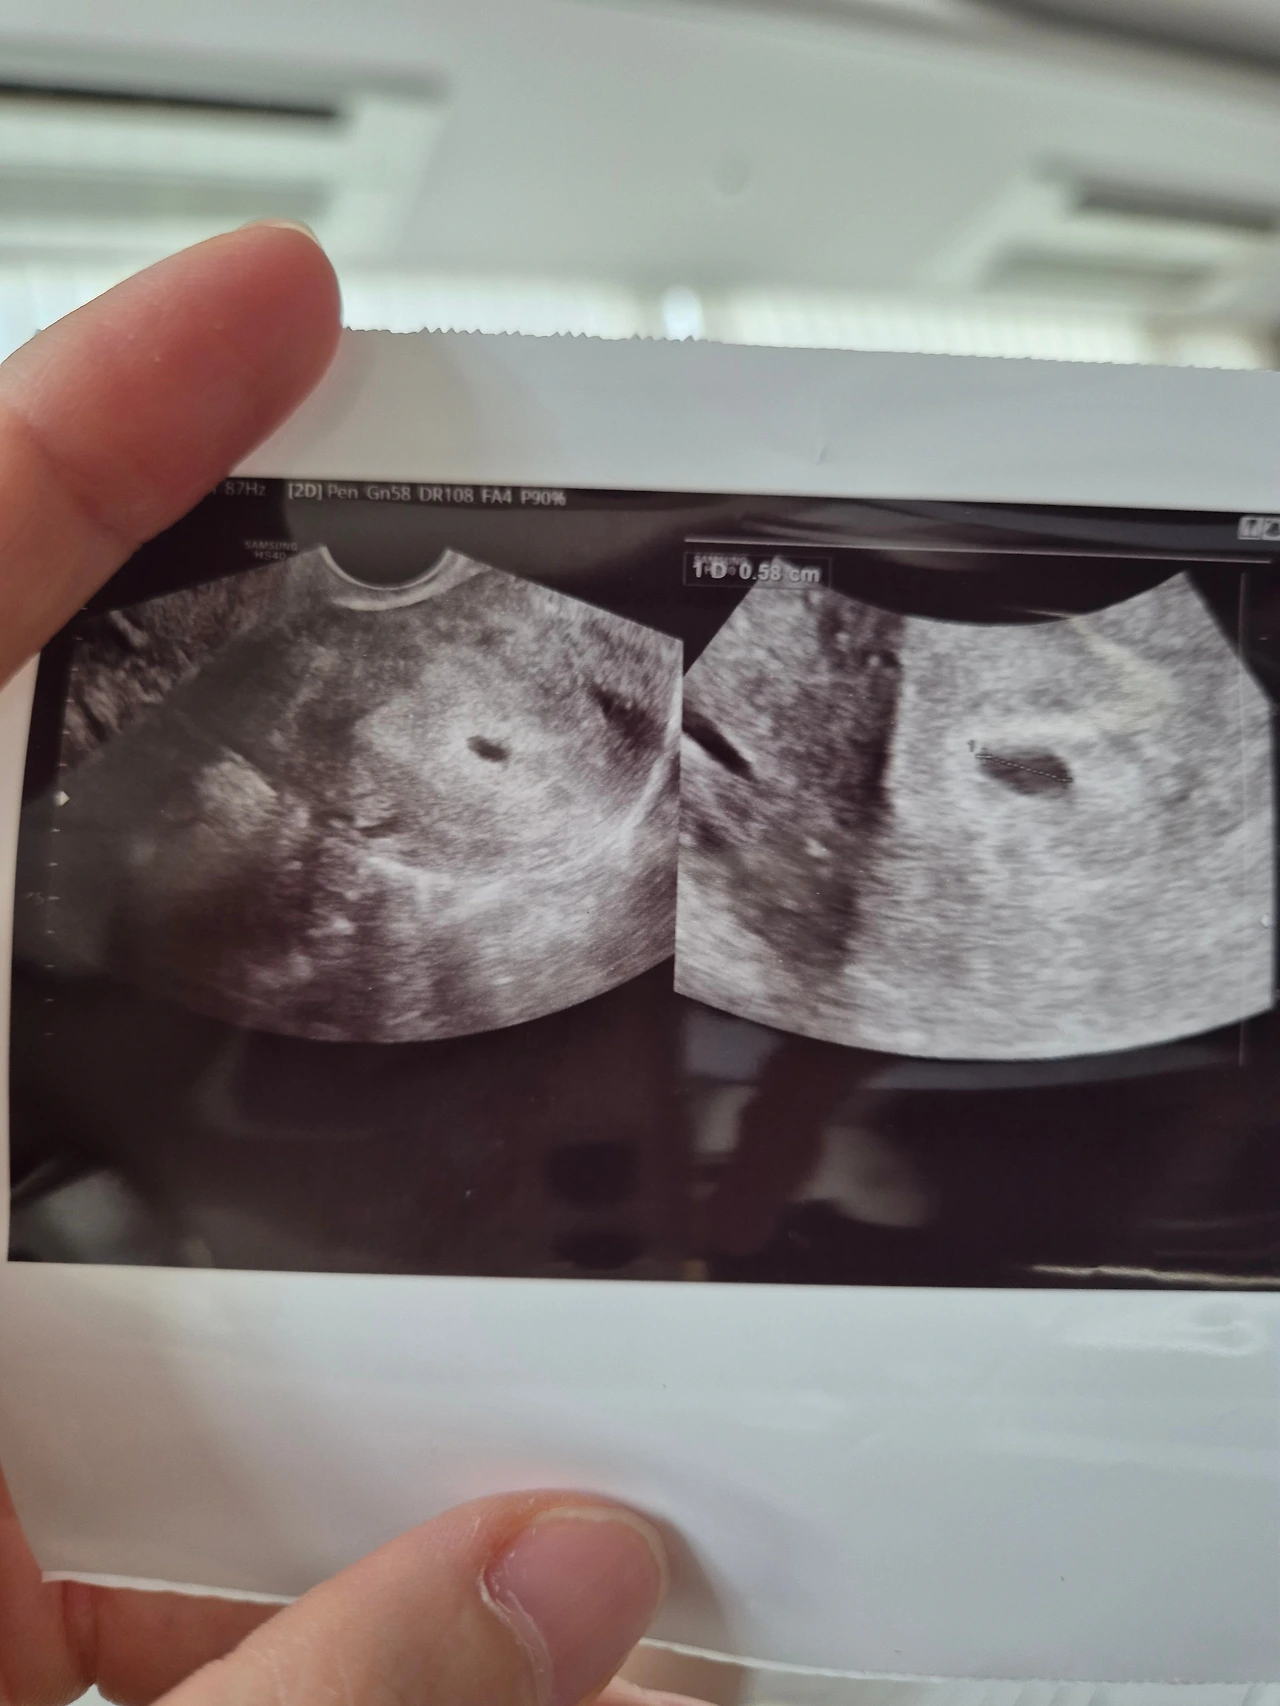

1시간여를 대기한 끝에 초음파를 보았는데, 아기집이 또렷하게 보였다.

하지만 S가 시험관 카페에서 자주 본 아기집의 모습과는 사뭇 달랐다.

동그랗다고 하기엔 몇 군데가 찌그러져있었다.

"찌그러져있긴 하지만 크기는 좋고요, 피고임이 좀 있네요. 안정을 취하셔야겠어요."

의사는, 아기집인지 피고임인지 아직 분별할 수 없는 어떤 동그라미가 하나 더 있다고 덧붙였다.

질 초음파를 보는 동안 Y는 복도에서 대기하고 있어야 했는데, S는 Y가 섭섭해할까 봐 초음파 사진을 갖고 나와 냉큼 보여주었다.

"아기집 안에 피가 고여있군요."